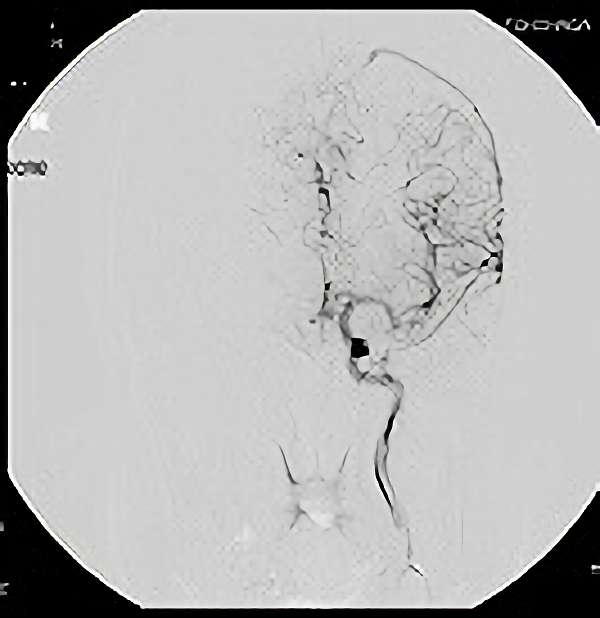

脳血管撮影

手術前

手術後